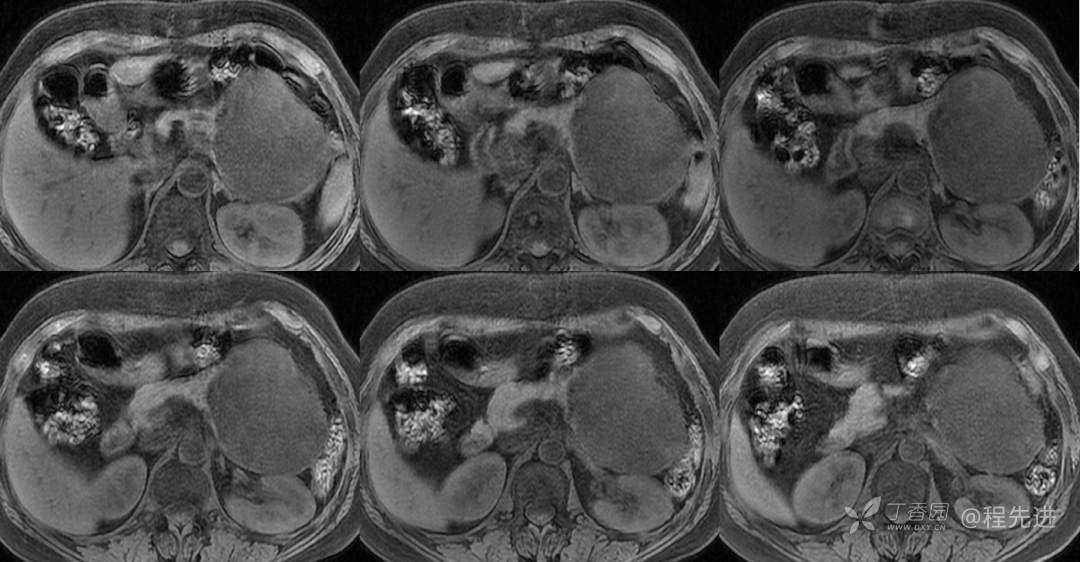

MR

T1压脂

T2压脂

DWI

ADC

ADC 值:2.8×10-3mm2/s